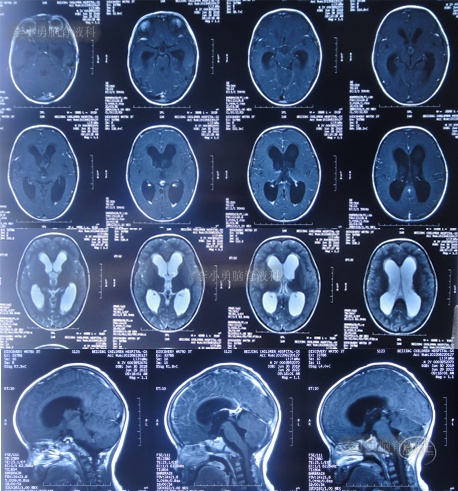

住院治疗7天即2022年5月18日,出现头痛,呕吐,体温再次升高为39.6度,心电图示室性心动过速,室早,考虑“心肌炎”,查头颅核磁(图-1)后并行腰穿见脑脊液呈金黄色,留取脑脊液送常规化验提示诊断为颅内感染,给予抗感染治疗。

图-1:2022年5月18日头颅核磁